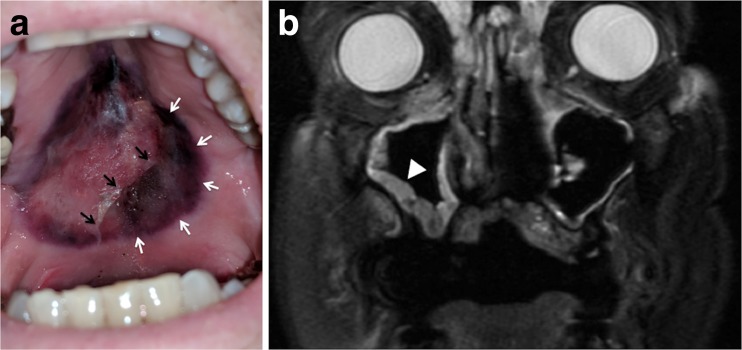

Fig. 1.

a Photograph of the patient’s hard palate showing an ulcerative lesion with necrotic eschar (white arrows) and sloughing necrotic mucosa (black arrows). b Magnetic resonance imaging showing diffuse paranasal sinus mucosal thickening, most prominent on the right (arrowhead).

A 75-year-old man with refractory acute lymphoblastic leukemia was hospitalized for dyspnea, hypotension, and neutropenia (< 0.10 × 109/L). Four weeks earlier, he initiated treatment with inotuzumab ozogamicin (an anti-CD22 antibody-drug conjugate). Home medications included prophylactic voriconazole, acyclovir, and trimethoprim-sulfamethoxazole. Computed tomography of the chest showed scattered pulmonary masses up to 3 cm in diameter. Bacterial and fungal cultures from blood and bronchoalveolar lavage were sterile. His condition improved with vancomycin, cefepime, and isavuconazole. On hospital day 16, he reported mouth pain. Examination revealed bilateral maxillary sinus tenderness and an ulcerative hard palate lesion with necrosis (Fig. 1 panel a). Absolute neutrophil count was 0.02 × 109/L. Magnetic resonance imaging showed diffuse paranasal sinus mucosal thickening (Fig. 1 panel b). Palatal biopsy and culture confirmed angioinvasive mucormycosis. Rhino-orbital-cerebral mucormycosis develops following the inhalation of fungal spores by an immunocompromised host. Palatal mucormycosis reflects tissue invasion from paranasal sinus infection and is a sign of aggressive disease portending a poor prognosis.1,2 Palatal ulceration, necrosis, and perforation can result.2 Treatment for rhino-orbital-cerebral mucormycosis (with or without palatal invasion) is intravenous antifungal therapy and surgical debridement.3 Resection was too morbid given the poor prognosis of his refractory leukemia. Amphotericin B and caspofungin were administered without improvement. The patient died 1 week later.